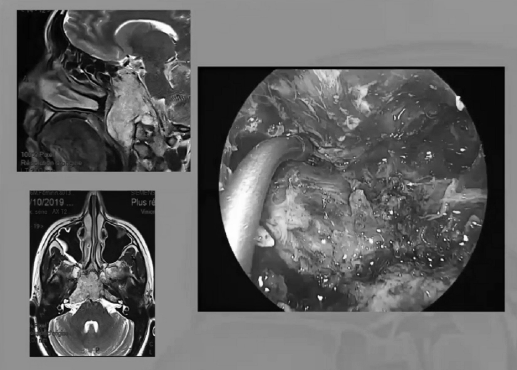

“筷子手法”经鼻内镜入路处理颅颈交界区肿瘤

从内镜我们怎样暴露颅颈交界区,需要把后方的咽部的黏膜和肌肉移开,如果我们要往侧方走的话,这比较具有挑战性,需要切掉一半的下方的结节,我们需要切除更多的黏膜,更多的肌肉,还需要磨掉翼板的内侧,要注意颈内动脉的二个膝部,还得切除一部分的咽鼓管,还得磨除一部分的枕髁,才能到达侧方,这样是很耗精力的。

▼这是几年前做的一个手术,先把鼻中隔先推开,然后推开那些正常的组织,这里磨掉枕髁,暴露舌下神经管。虽然很具有挑战性,但是手术做得还是不错的,我们对病人进行了长期的随访,因为我们把全部的就是切开的软组织都复位了,所以看起来还可以,经过内固定以后,病人的颅颈交界区是很稳定的。